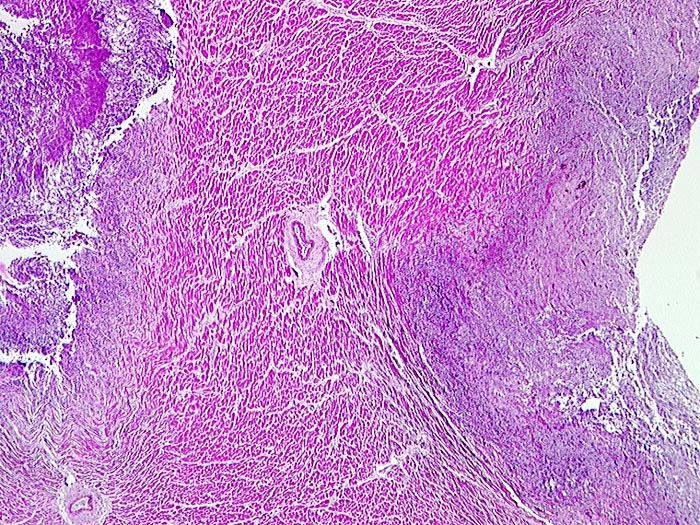

Septisch embolische Myokarditis: Aspergillussepsis

Entzündung infektiös

Kardiovaskuläres System

Ausgedehnte Myokardnekrosen (blaue Areale)

Septische Herde in Haut, Nieren und Herz

Chronische lymphatische Leukämie. St.n. Chemotherapie. Steroiddauertherapie.